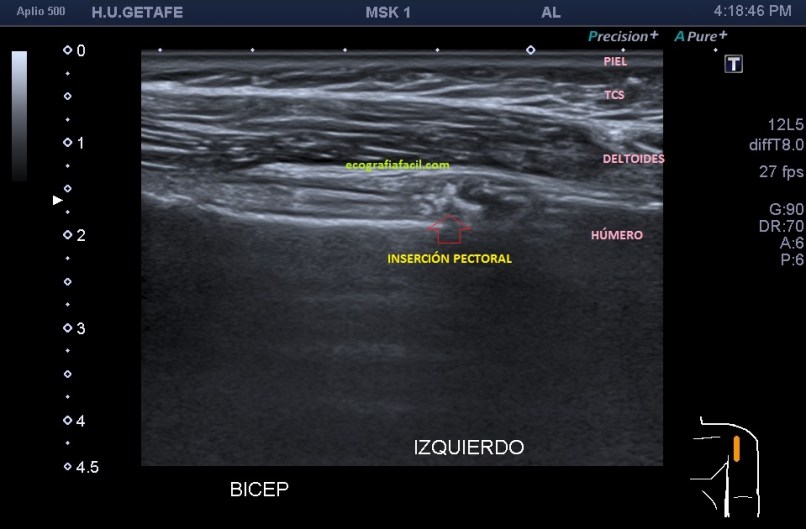

El caso es de una mujer que acude por omalgia, en la exploración del tendón del bíceps no observo nada reseñable, pero en el recorrido exploratorio al llegar al lugar de inserción del pectoral, observo una imagen irregular, hiperecogénica con una ligera sombra posterior, indolora para la paciente durante el transcurso de la exploración.

En muchas ocasiones, sobre todo en los talleres de ecografía muscular, los alumnos me preguntan dónde debemos de dejar de explorar el tendón del bíceps incluido en el estudio del hombro, y este lugar (inserción del pectoral) referido en este post, es el final.

Cuando veamos la inserción del tendón pectoral en el surco intertubercular de la corredera bicipital, sabemos que si no hay ninguna alteración locorregional, es el final del estudio del bíceps.

En la imagen número 1 ves normalidad, como siempre te digo, la normalidad como base para crecer, la imagen número 2 fue el hallazgo, y de verdad que lo fue, ya que aunque siempre lo miro nunca me encontré una imagen así y me sorprendió.

Observa la imagen 1 y la 2 para ver cómo tienes que ver el tendón, te lo marco con lineas amarillas para ayudarte si tienes dificultad para poder verlo ya que es una ecoestructura muy fina, por eso, cuando explores esta región, ten cuidado no vayas pasarla por alto.